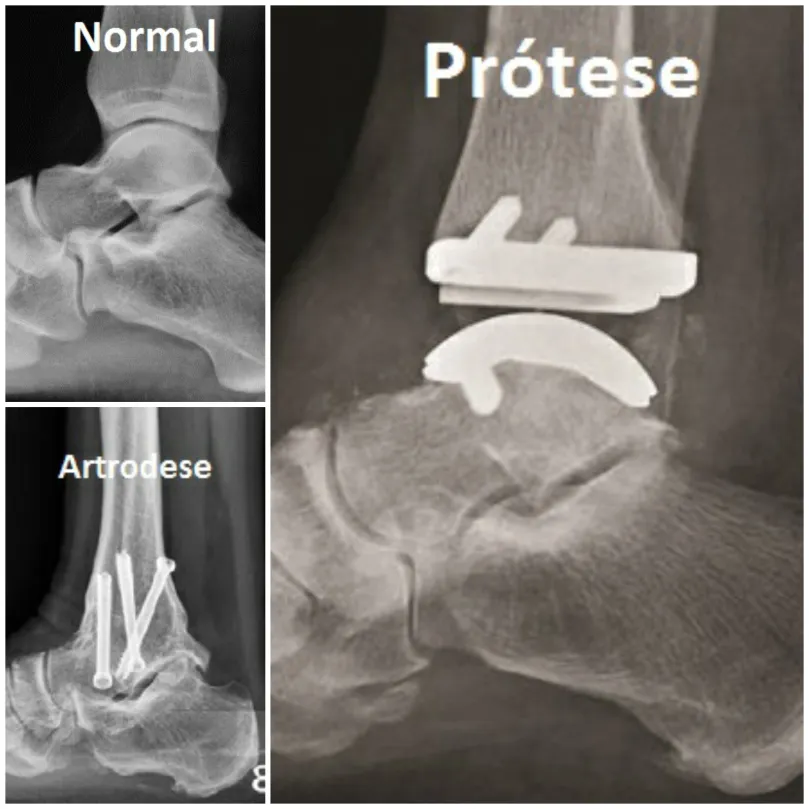

Até pouco tempo atrás, o tratamento mais indicado para artrose grave do tornozelo era a cirurgia de artrodese, quando se realiza uma fusão entre os ossos da articulação. Com isso, havia melhora da dor, porém o paciente perdia o movimento do tornozelo.

Hoje em dia, em grande parte dos casos, realizamos a artroplastia do tornozelo, quando se faz a substituição da articulação doente (tornozelo com artrose) por uma articulação metálica (prótese de tornozelo). Neste tipo de tratamento obtemos a melhora da dor com a manutenção do movimento articular.